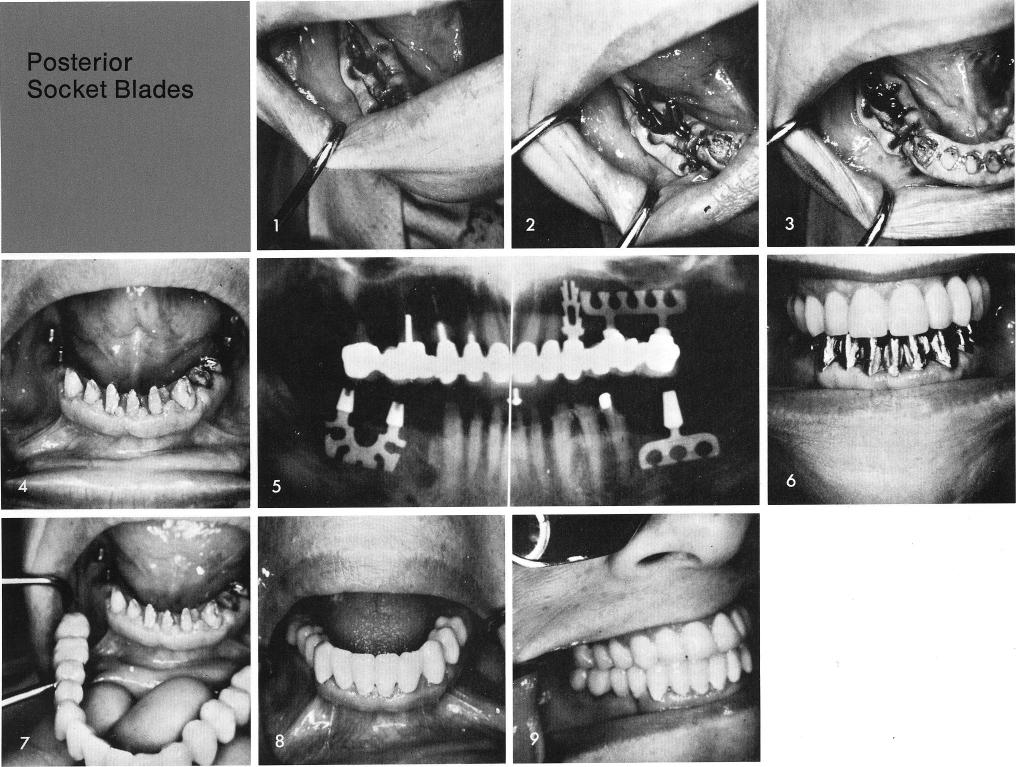

As long as there is healed bone mesially and distally that flanks a socket created from an extracted tooth, screw type implants or vitreous carbon implants or a bladevent implant can be immediately inserted, fig. 1. The "socket" bladevent must, however, be tapped in such a manner that the recessed shoulder is at least 2 mm. below the lowest cortical plate that exists which is usually the buccal and both posts must rest on the alveolar crest mesial and distal to the socket, figs. 2, 3. In this manner bone will definitely grow over the shoulder of the blade and the soft tissues will heal uneventfully, fig. 4. An immediate x-ray shows the socket blade properly inserted, fig. 5. Castings are fabricated, fig. 6, and the completed prosthesis is completed and cemented, figs. 7, 8, 9. A final x-ray, fig. 10.

1 screw type or vitreous carbon or a bladevent implant in mandible